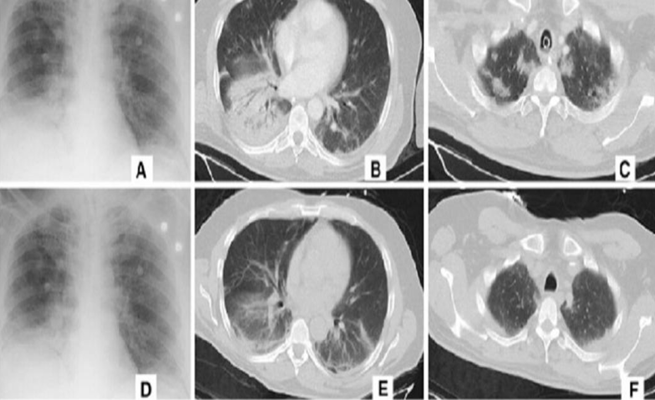

وفقاً لتقرير لموقع “Nikkei’s Asian Review”، تدّعي شركة “Alibaba” أن نظامها الجديد يمكنه اكتشاف الفيروس التاجي في فحوصات الأشعة المقطعية لصدور المرضى ورصد حالات الالتهاب الرئوي الفيروسي.

ووفق ما اوردت “الخليج أونلاين”، يستغرق تشخيص الذكاء الاصطناعي للمرض 20 ثانية فقط، وفقاً للتقرير، بينما يستغرق الأطباء بالتحاليل الاعتيادية عموماً نحو 15 دقيقة، حيث يمكن أن يوفر أكثر من 300 صورة للتقييم.

وتقول الشركة: “تم تدريب النظام على الصور والبيانات من 5000 حالة إصابة بالفيروس التاجي، وتم اختباره بالفعل في المستشفيات بجميع أنحاء الصين، وهناك 100 منشأة للرعاية الصحية على الأقل تستخدم حالياً شركة Alibaba’s AI”.